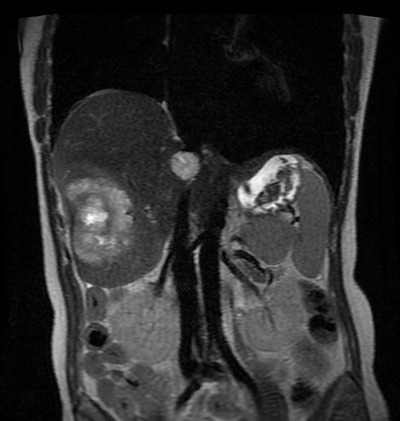

Vous avez donc fait réaliser l’examen suivant (figure 3) : Fig. 3 (source : M. Roulleaux Dugage)

Question 7 - Concernant cet examen, vous pouvez dire que :

Il s’agit d’une IRM hépatique en séquence T2, montrant une lésion du VI et une lésion du VIII avec tout l’aspect d’une métastase ou de tout processus inflammatoire : – hyposignal T1 (dans le cas d’une métastase, réhaussement après l’injection de produit de contraste) ; – hypersignal T2. L’IRM hépatique est à demander devant toute lésion hépatique de cancer du côlon, afin d’en évaluer la résécabilité.

Mme P. a donc été opérée en semi-urgence d’une colectomie droite avec exérèse du mésocôlon. Les suites sont simples. Vous rediscutez du dossier en RCP. La coloscopie n’a pas montré d’autre lésion colique. L’IRM hépatique met en évidence au total deux lésions hépatiques d’allure secondaire, d’allure résécable. L’anatomopathologie met en évidence un adénocarcinome lieberkühnien de 11 cm envahissant la séreuse, sans envahissement ganglionnaire (0N/11), pas d’envahissement périnerveux ou d’embole lymphatique, R0. La biologie moléculaire montre une tumeur KRAS sauvage, MSS. L’antigène carcino-embryonnaire (ACE) postopératoire est à 28,7 U/L (N < 5U/L).